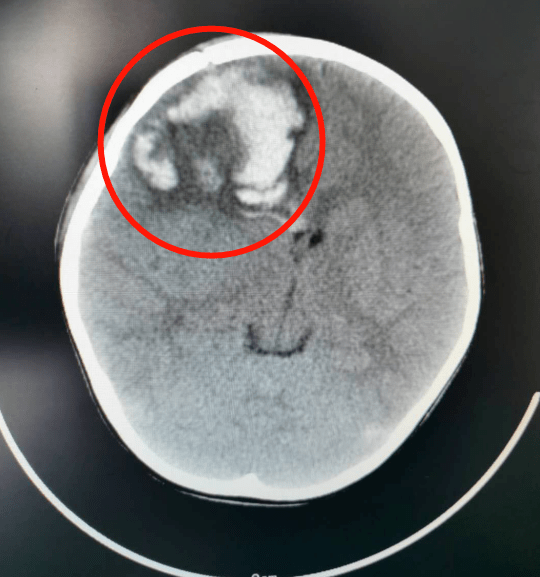

患者:赵宇楠,女,22岁,右侧额顶叶脑出血,神清语明,左侧肢体瘫痪